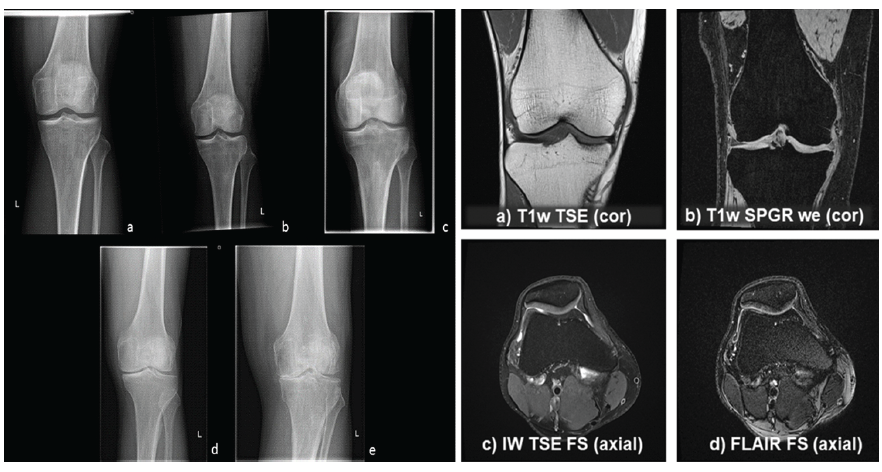

Cartilage compositional imaging

T2 mapping demonstrated prolonged relaxation times in degenerated cartilage regions, indicative of collagen network disruption and increased water content. The mean T2 relaxation time in affected regions was 42.8 ± 6.2 ms, compared to 33.4 ± 4.1 ms in normal-appearing cartilage. T1ρ mapping revealed a mean value of 48.6 ± 7.1 ms in degenerated cartilage versus 35.7 ± 5.0 ms in healthy cartilage, reflecting early proteoglycan depletion (Table 1 and Fig. 1).

Figure 1: Magnetic resonance imaging cartilage parameters.